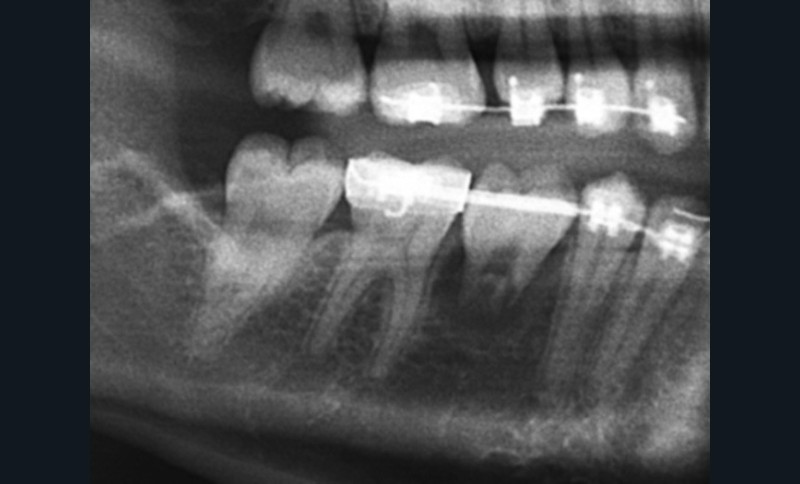

Véritable marronnier de l’orthodontie, la transplantation est proposée depuis longtemps mais ne s’est pas vulgarisée. Pourtant, les cas cliniques proposés sont encourageants. En effet, le taux de réussite pour les dents immatures est élevé : 97 % à 5 ans, contre 95 % pour les implants [7, 8, 9]. Cela fait de la transplantation une alternative thérapeutique crédible à l’implant qui montre ses limites (péri-implantites…) sur le long terme. Bien sûr, la transplantation peut être suivie d’échecs : ankylose, résorption, nécrose pulpaire [9]. Néanmoins, elle permet de conserver l’os alvéolaire, parfois d’autoriser des légers mouvements dentaires orthodontiques des transplants et de conserver la proprioception. Elle peut, au pire, constituer une solution transitoire permettant d’attendre la fin du traitement orthodontique et la pose de l’implant prévu à la fin de la croissance (fig. 1).

La 3e molaire peut être utilisée en place…